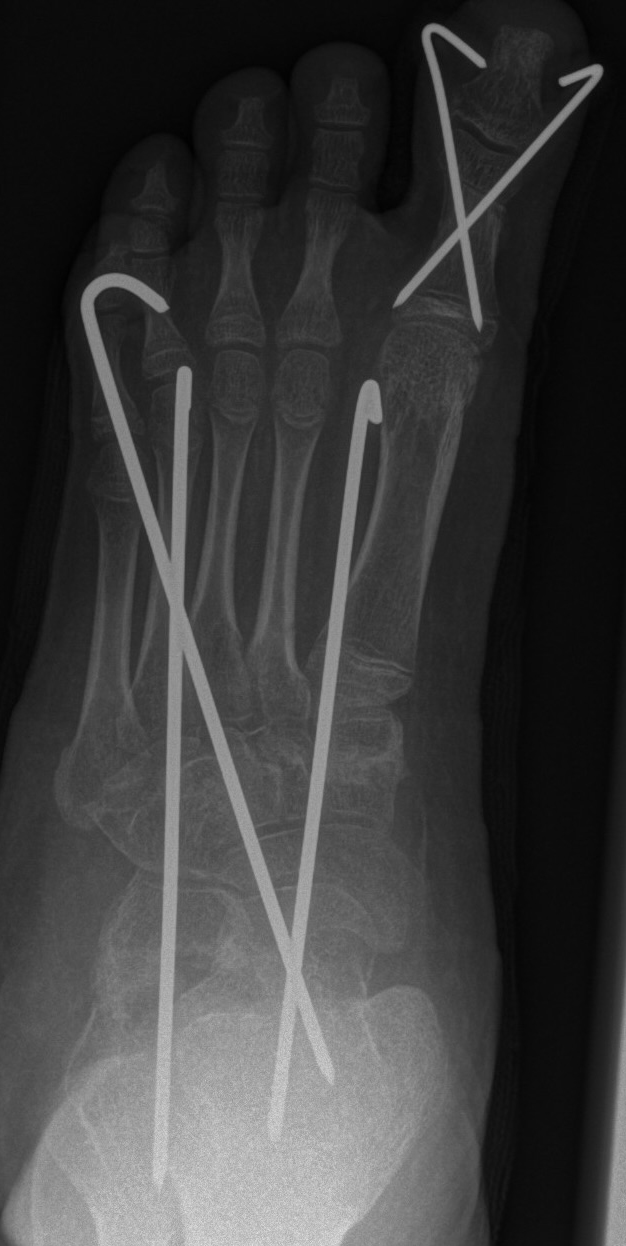

Calcaneus-Osteotomie

Die minimalinvasive Calcaneusverschiebeosteotomie bietet eindeutige Vorteile gegenüber dem offenen Verfahren, sodass wir bei Kindern und Jugendlichen nahezu keine offene Verschiebeosteotomie mehr durchführen. Am Calcaneus liegt die offene Wachstumsfuge dorsal. Bei der Durchführung müssen Schenkel der V-förmigen Osteotomie daher etwas steiler angelegt werden, in einem stumpfen Winkel (siehe Abb. 3 a-j). Für die Osteotomie liegen unsere Patienten auf dem Rücken und der BV wird für die exakte Seitaufnahme eingestellt. Der Fuß lagert auf einem hohen OP-Kissen und die Osteotomie kann bequem mit einem langen Kirschner-Draht und einem sterilen Stift angezeichnet werden (Abb. 15).

Damit lässt sich im Verlauf Röntgenstrahlung für die jungen Patienten vermeiden und die minimalinvasive Osteotomie kann sicher durchgeführt werden. Anschließend erfolgt die Verschiebung oder Impaktion. Ist ein Gleiten nach plantar oder cranial des distalen Fragmentes erwünscht, wird die Osteotomie schräg ohne V-Form entweder verlängernd oder verkürzend durchgeführt (Abb. 16).

Durch den knöchernen Defekt der Fräse gelingt die Verschiebung bei der minimalinvasiven Osteotomie im Fall von strukturell festen Klumpfüßen mit starkem Zug der verkürzten Achillessehne oder bei einer fixierenden spastischen Grunderkrankung einfacher gegenüber dem offen Verfahren. Ein weiteres Plus bei hyperaktiven Weichteilen ist die Vermeidung der ungewollten Cranialisierung des dorsalen Fragmentes durch die V-förmige Osteotomie (Abb. 16).

Die minimalinvasive Calcaneusverschiebeosoteotomie kommt somit in der Versorgung von kindlichen und jugendlichen Fußdeformitäten in einem weiten Erkrankungsspektrum zum Einsatz (Abb. 16):

- Plattfuß – Varisation

- Klumpfuß residual – Valgisation und ggfs. Cranialisation sowie Impaktion

- Klumpfuß überkorrigiert – Varisation und ggfs. Plantarisierung

- Hohlfuß – Cranialisation und ggf. Valgisation (alternativ minimalinvasive Austin-Osteotomie)

Abb. 16 a-f: Varisation einer valgischen Calcaneusstellung bei Knick-Senk-Fuß mit V-förmiger Osteotomie axiale Ansicht (a), seitliche Ansicht (b), d. p. Ansicht (c) und nach Entfernung der Drähte seitliche Ansicht (d), Caudalisierung des dorsalen Calcaneus bei iatrogenem Plattfuß nach Klumpfußüberkorrektur (e) und Cranialisierung beim Hohlfuß (f).

Zum Lesen der Bildbeschreibung und zur Vollansicht bitte die Bilder anklicken. Bilder: A. Helmers.